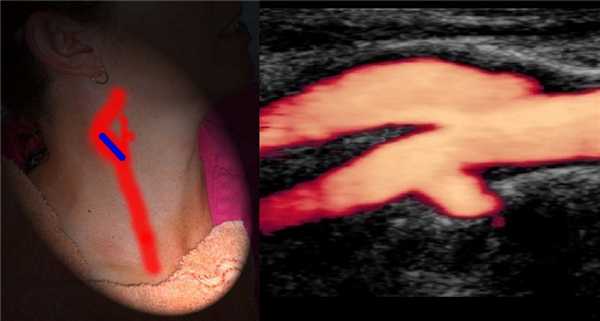

У бифуркации ОСА расширение луковицы, начинается голый ствол ВСА и ветвящаяся НСА. Первая ветвь НСА — верхняя щитовидная артерия.

На уровне бифуркации ВСА шире НСА; расположена кнаружи и кзади от НСА, выше перемещается кнутри; не имеет ветвей на шее.

В луковице ламинарный поток по основной оси ВСА красный, а зона турбулентного потока у наружной стенки окрашивается в синий.